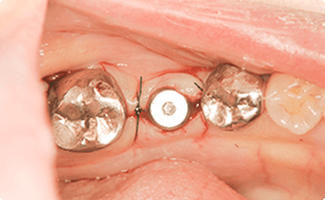

奥歯のインプラントの症例

ブリッジが壊れて奥歯を失った方

BEFORE

AFTER

症例概要

年代・性別

40歳代 女性

主訴

奥歯がグラグラする

治療内容

下顎両側6番 インプラント治療、左下5番セラミッククラウン(デジタル)

治療期間

3ヶ月

治療のリスク

インプラント周囲炎のリスクがあるため、メンテナンスに来ていただきます。

治療費用

913,000円(税込)